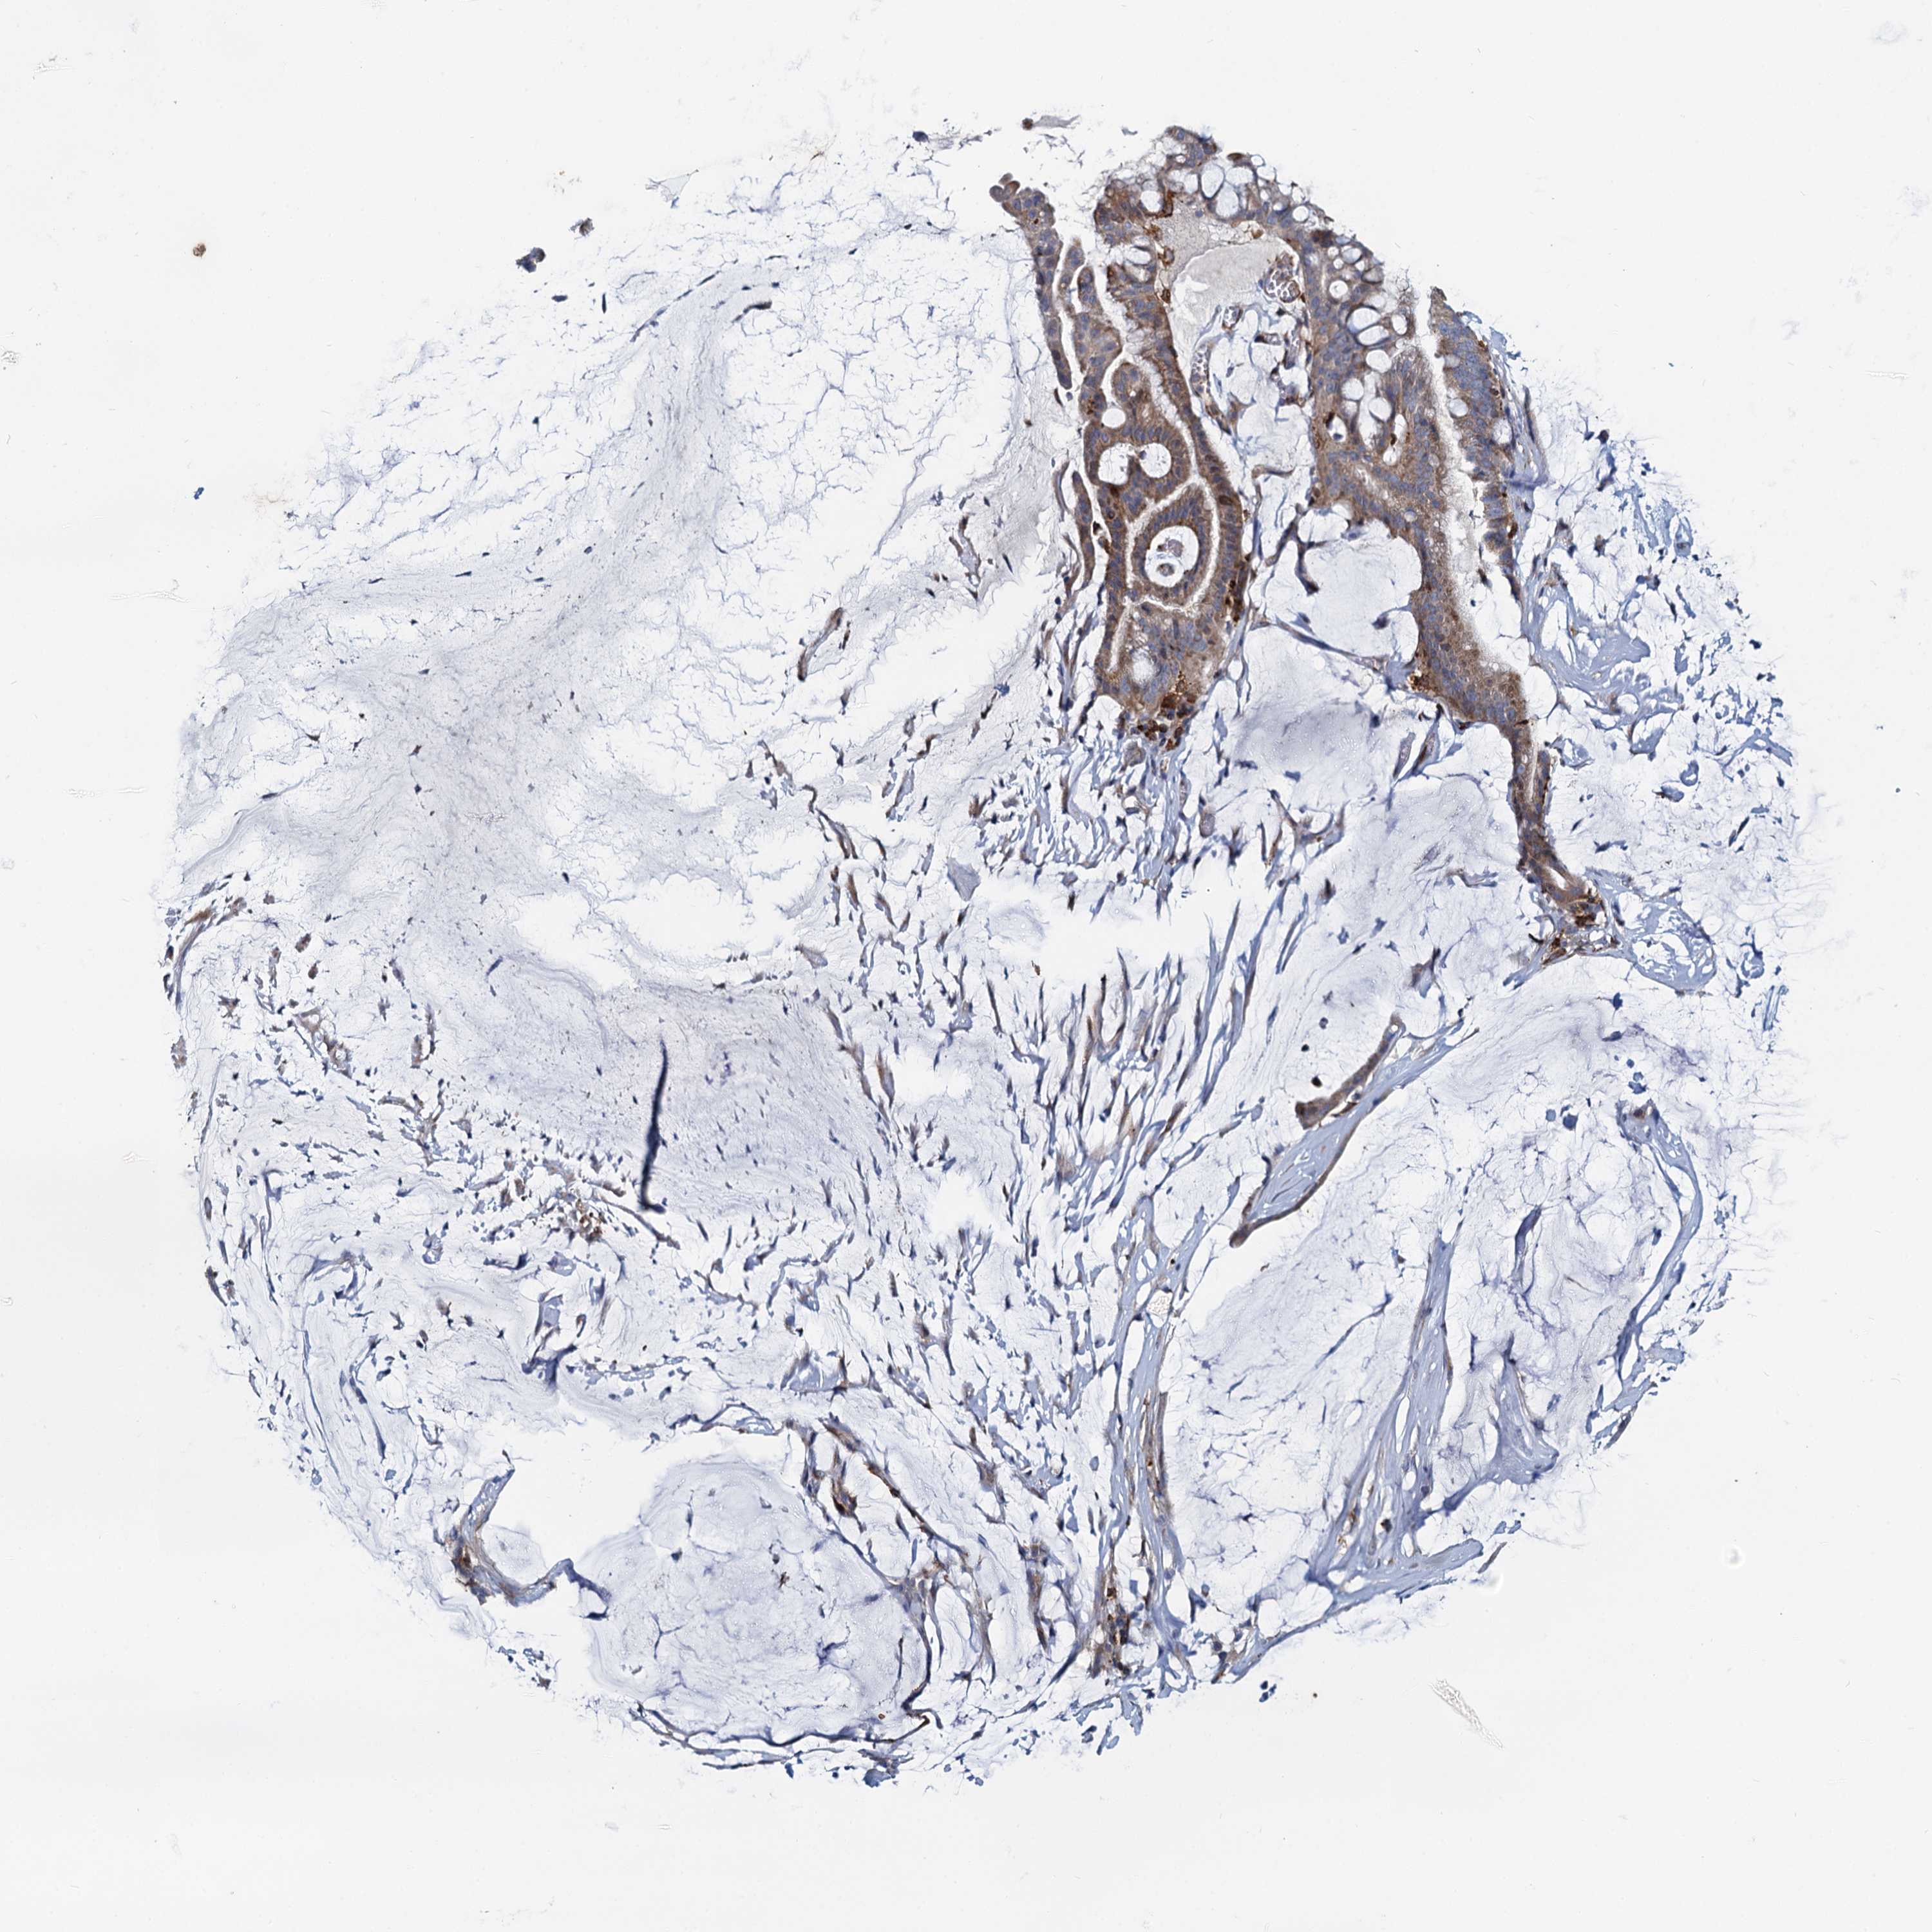

OVARIAN CANCER - Protein expressioni

A mouse-over function shows sample information and annotation data. Click on an image to view it in a full screen mode. Samples can be filtered based on level of antibody staining by selecting one or several of the following categories: high, medium, low and not detected. The assay and annotation is described here.

Note that samples used for immunohistochemistry by the Human Protein Atlas do not correspond to samples in the TCGA dataset.

Antibody stainingi

Antibody staining in the annotated cell types in the current human tissue is reported as not detected, low, medium, or high, based on conventional immunohistochemistry profiling in selected tissues. This score is based on the combination of the staining intensity and fraction of stained cells.

Each image is clickable and will lead to virtual microscopy that enables deeper exploration of all samples and also displays staining intensity scores, fraction scores and subcellular localization as well as patient and tissue information for each sample.

Antibody HPA039349

Staining

High

Medium

Low

Not detected

Intensity

Strong

Moderate

Weak

Negative

Quantity

>75%

75%-25%

<25%

None

Location

Nuclear

Cytoplasmic/membranous

Cytoplasmic/membranous,nuclear

Cystadenocarcinoma, serous, NOS

Carcinoma, endometroid

Cystadenocarcinoma, mucinous, NOS

Carcinoma, NOS